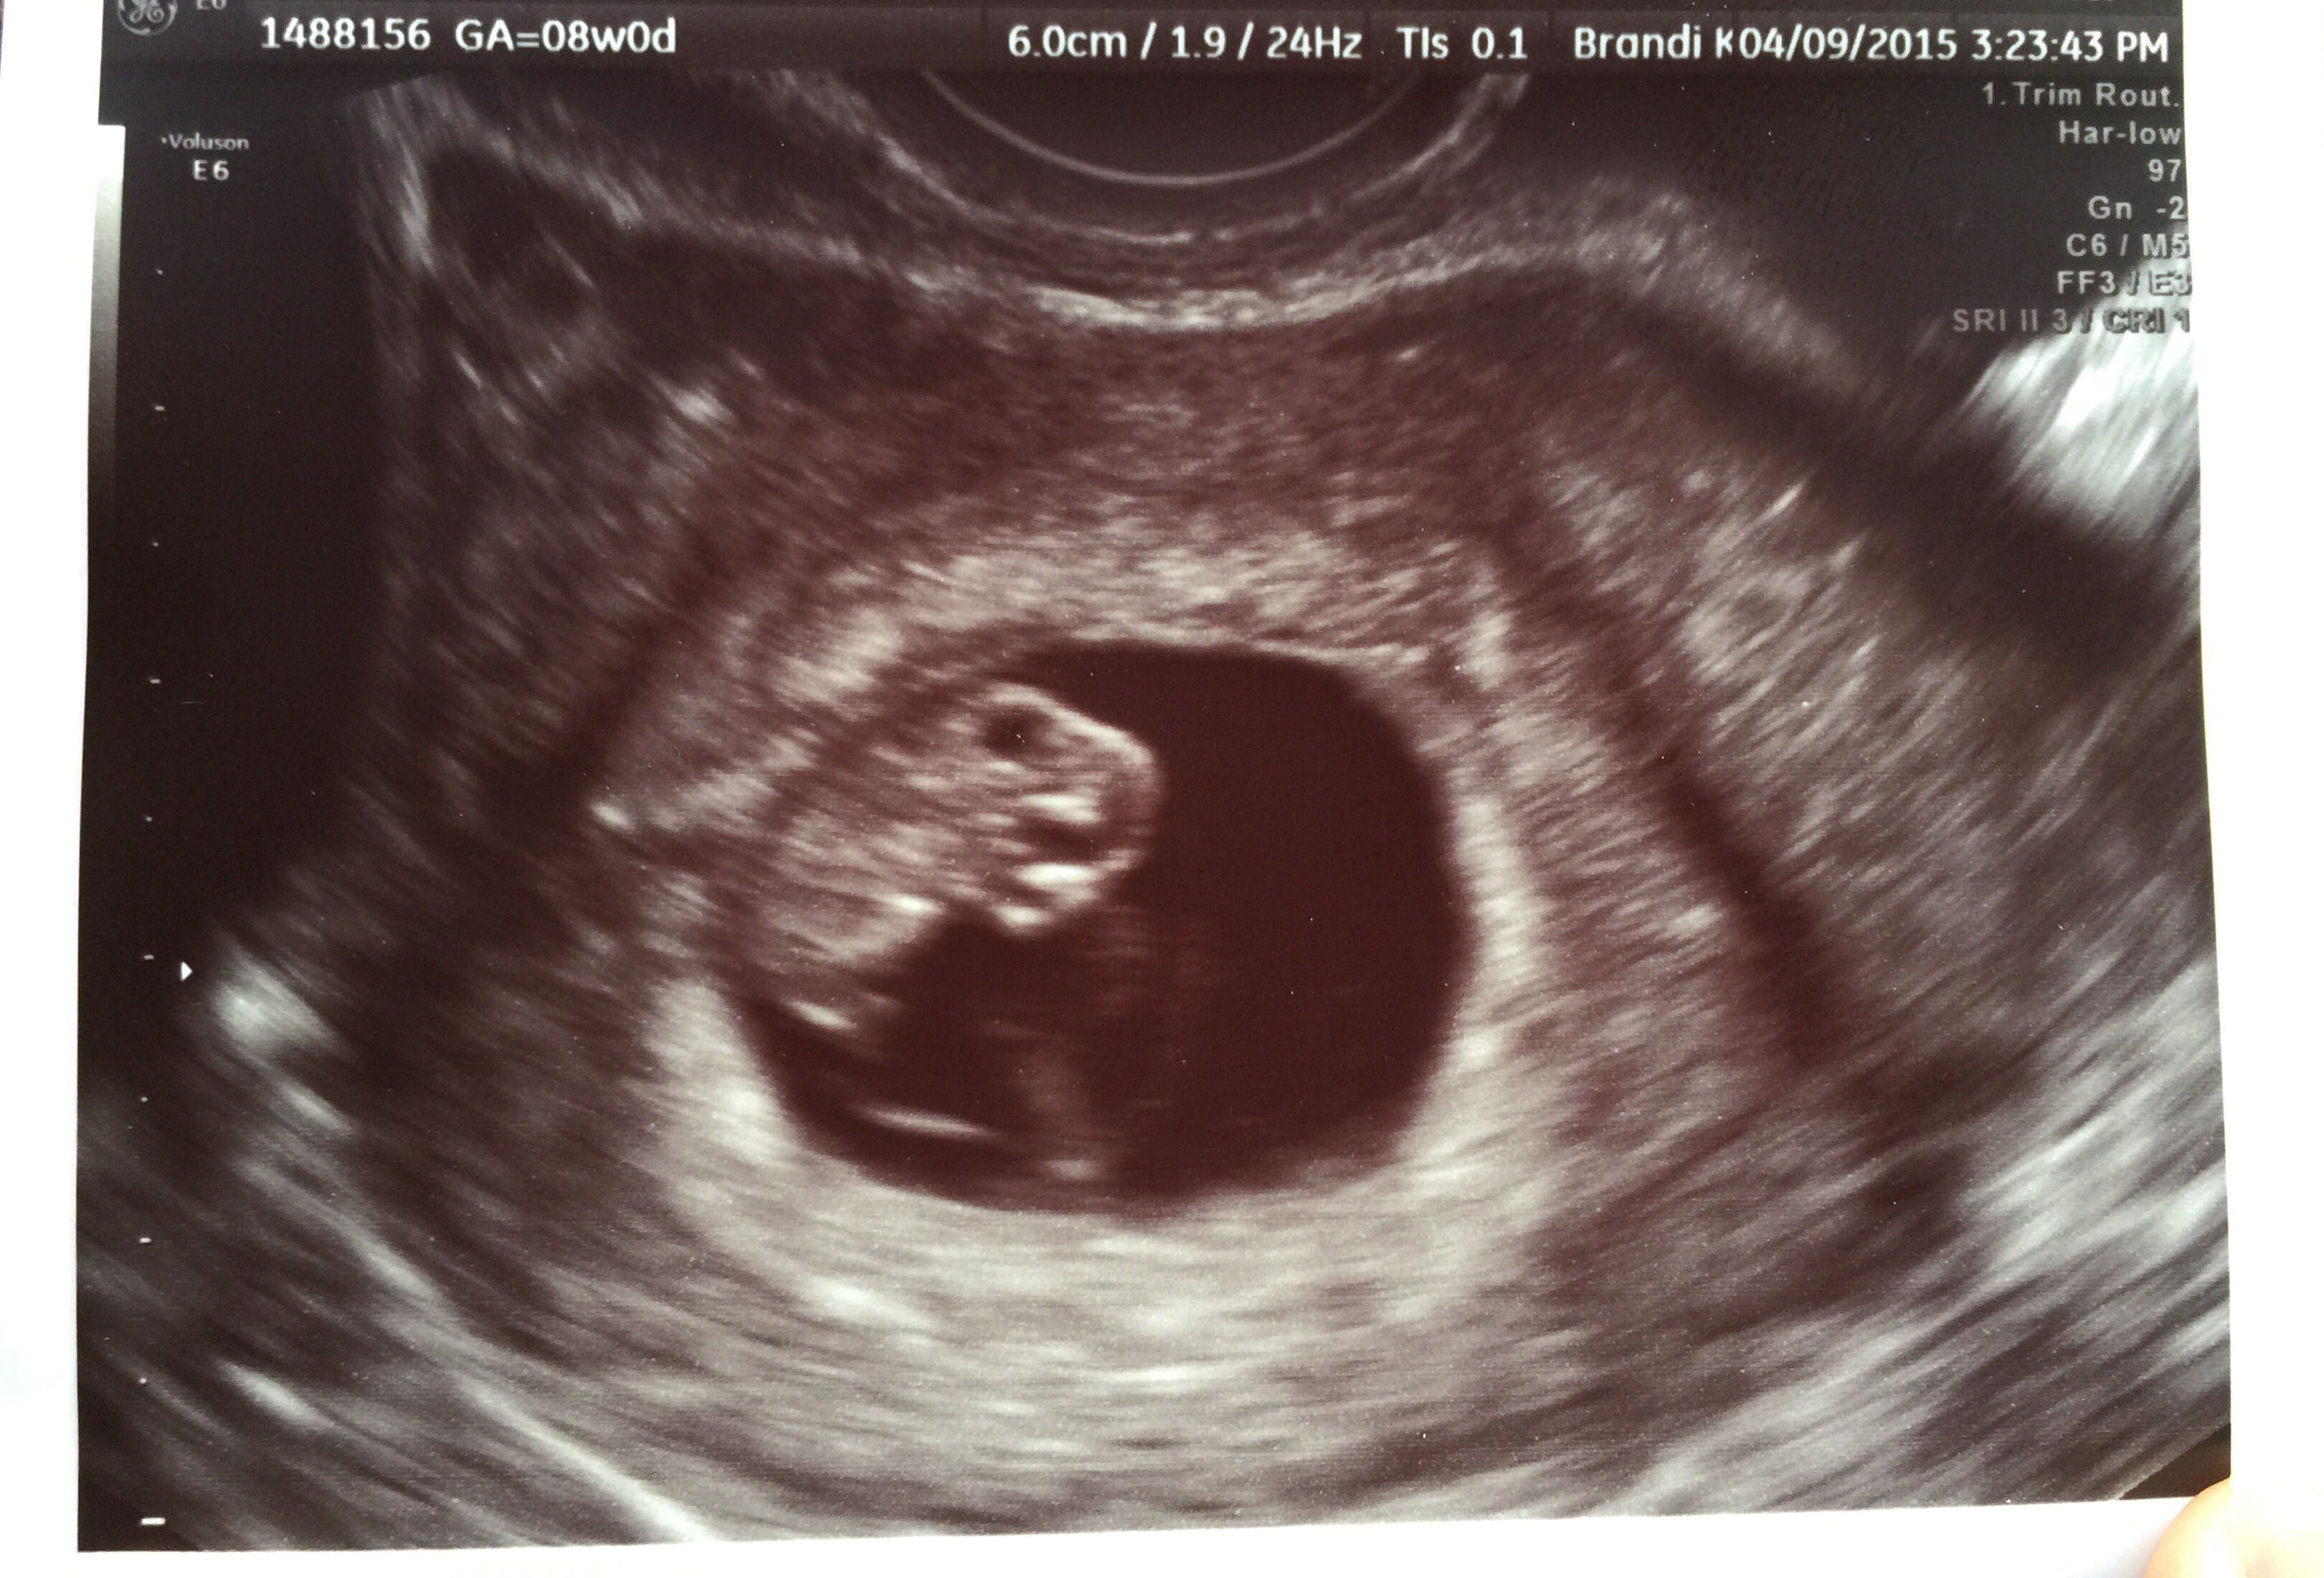

Here is our second ultrasound! 8w0d to check on twins. Unfortunately we lost our second baby. On a good note, we have one strong healthy baby with a heartbeat of 178!!